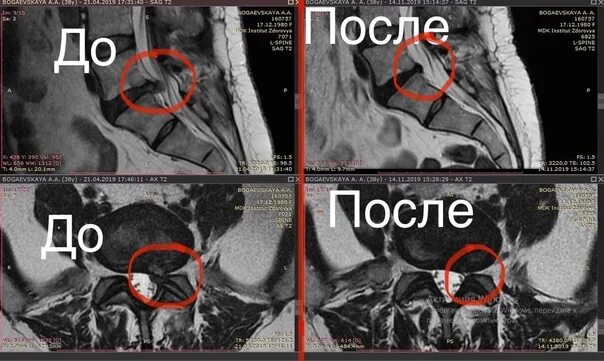

Резорбция епифанов